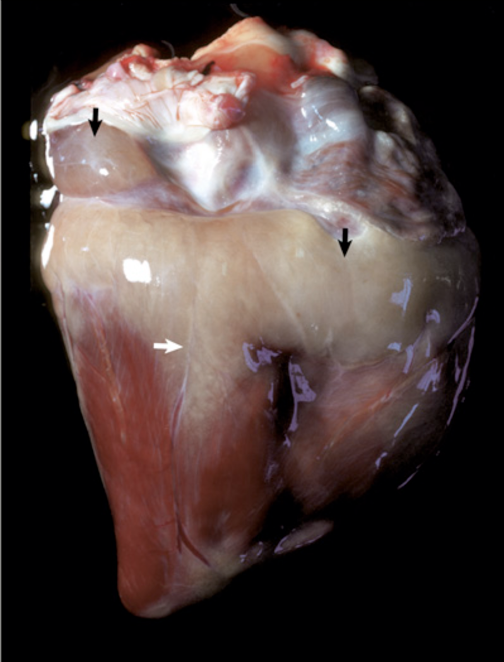

What is affecting this cavalier king charles spaniel’s heart? note the off white nodular thickenings around the AV valve leaflets.

valvular endocardiosis (myxomatous valvular degeneration)